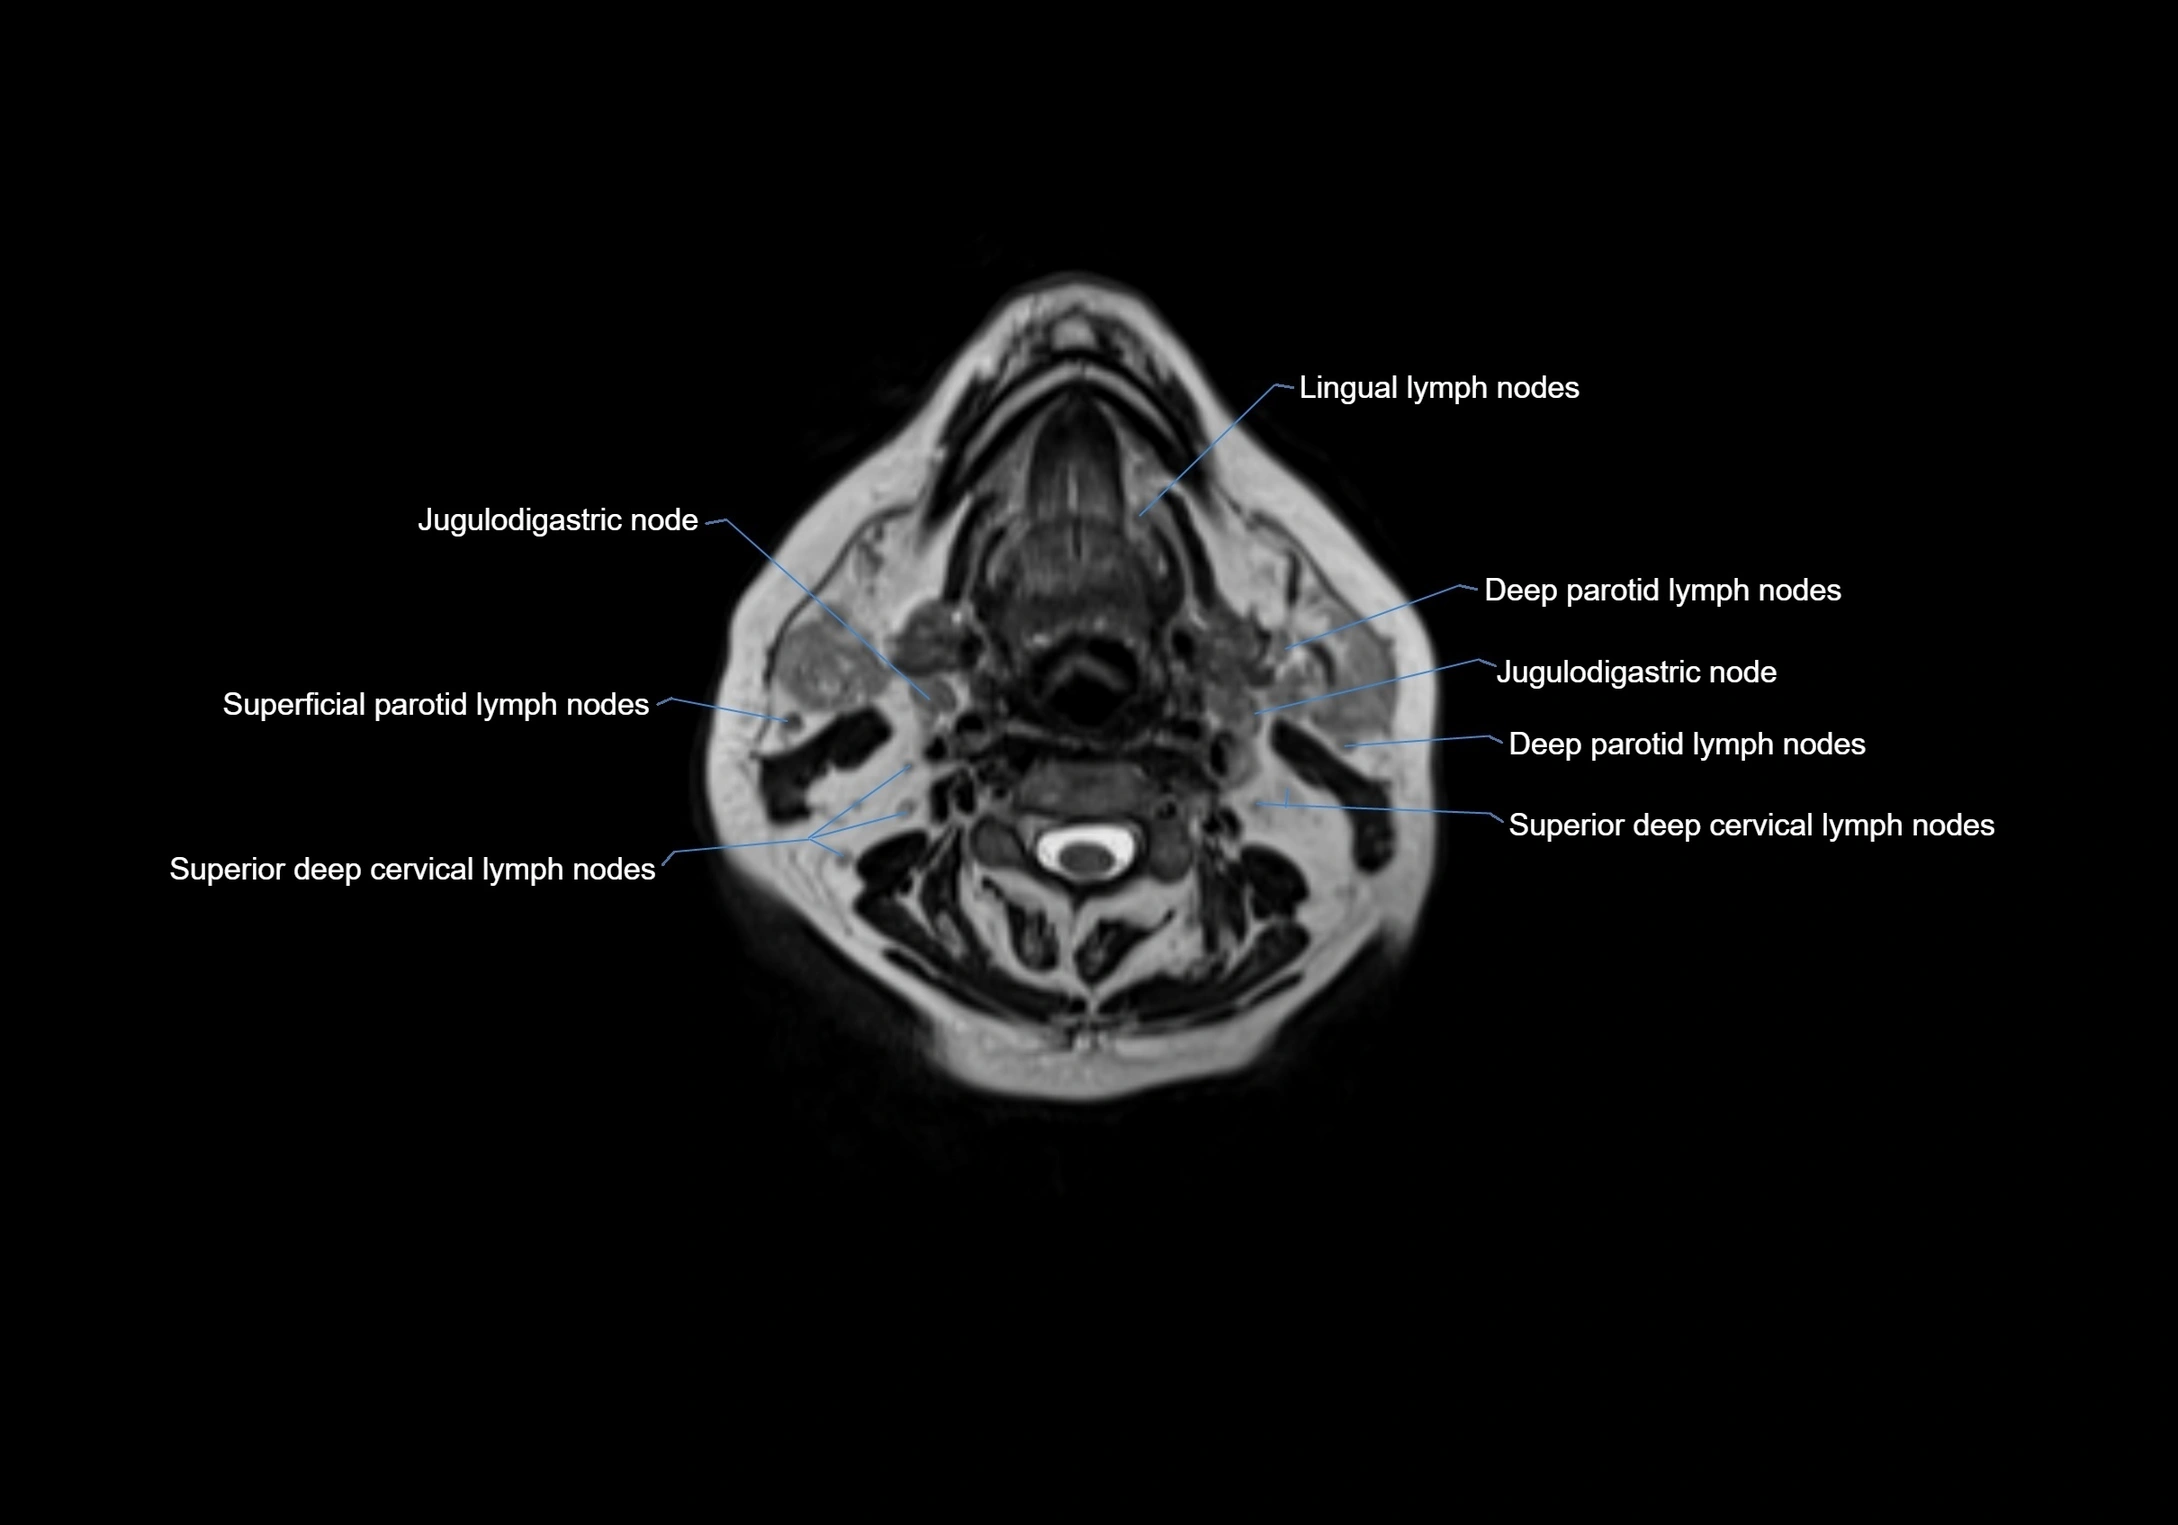

Location

• Found along primary lymph node chains, including preauricular, submandibular, parotid, and occipital regions

• Embedded in subcutaneous fat or superficial fascia, often lateral or posterior to primary nodes

• Variable in number; may occur unilaterally or bilaterally, depending on individual anatomy

MRI images